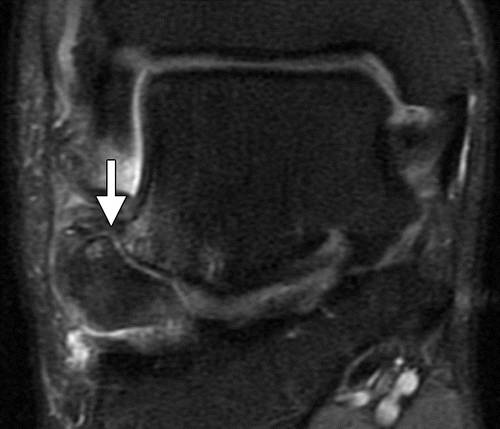

图18a距骨横突骨折的不愈合。 (a)踝的AP射线照片显示侧向过程的皮质骨折片段(箭头),与不连续的横突骨折(霍金斯I型)一致。 (b)踝的冠状质子密度加权的脂肪饱和MRI图像显示了横突的大的皮质片段,与非骨质断裂一致。 皮下水肿和囊肿存在于假关节(箭头)。